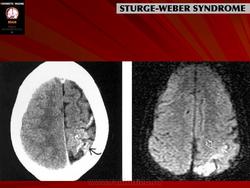

Магнитная резонансная томография пациента с болезнью Штурге - Вебера

Синдром Sturge-Weber.

Рентгенологически можно обнаружить обызвествление в затылочных и теменных отделах мозга. При ПЭГ у большинства больных отмечаются атрофия вещества мозга, расширение субарахноидальных щелей на конвекситальной поверхности и расширение полостей желудочков мозга.

Диагноз синдрома Стерджа - Вебера не представляет трудностей. Наличие корковых обызвествлений можно выявить при рентгенографии. Характерные тени располагаются в виде двойных контуров, повторяющих извилины пораженных долей мозга. Компьютерная томография выявляет более обширные области обызвествления, чем это видно при обычной рентгенографии.

Компьютерная томография пациента с болезнью Штурге - Вебера

Магнитная резонансная томография пациента с болезнью Штурге - Вебера